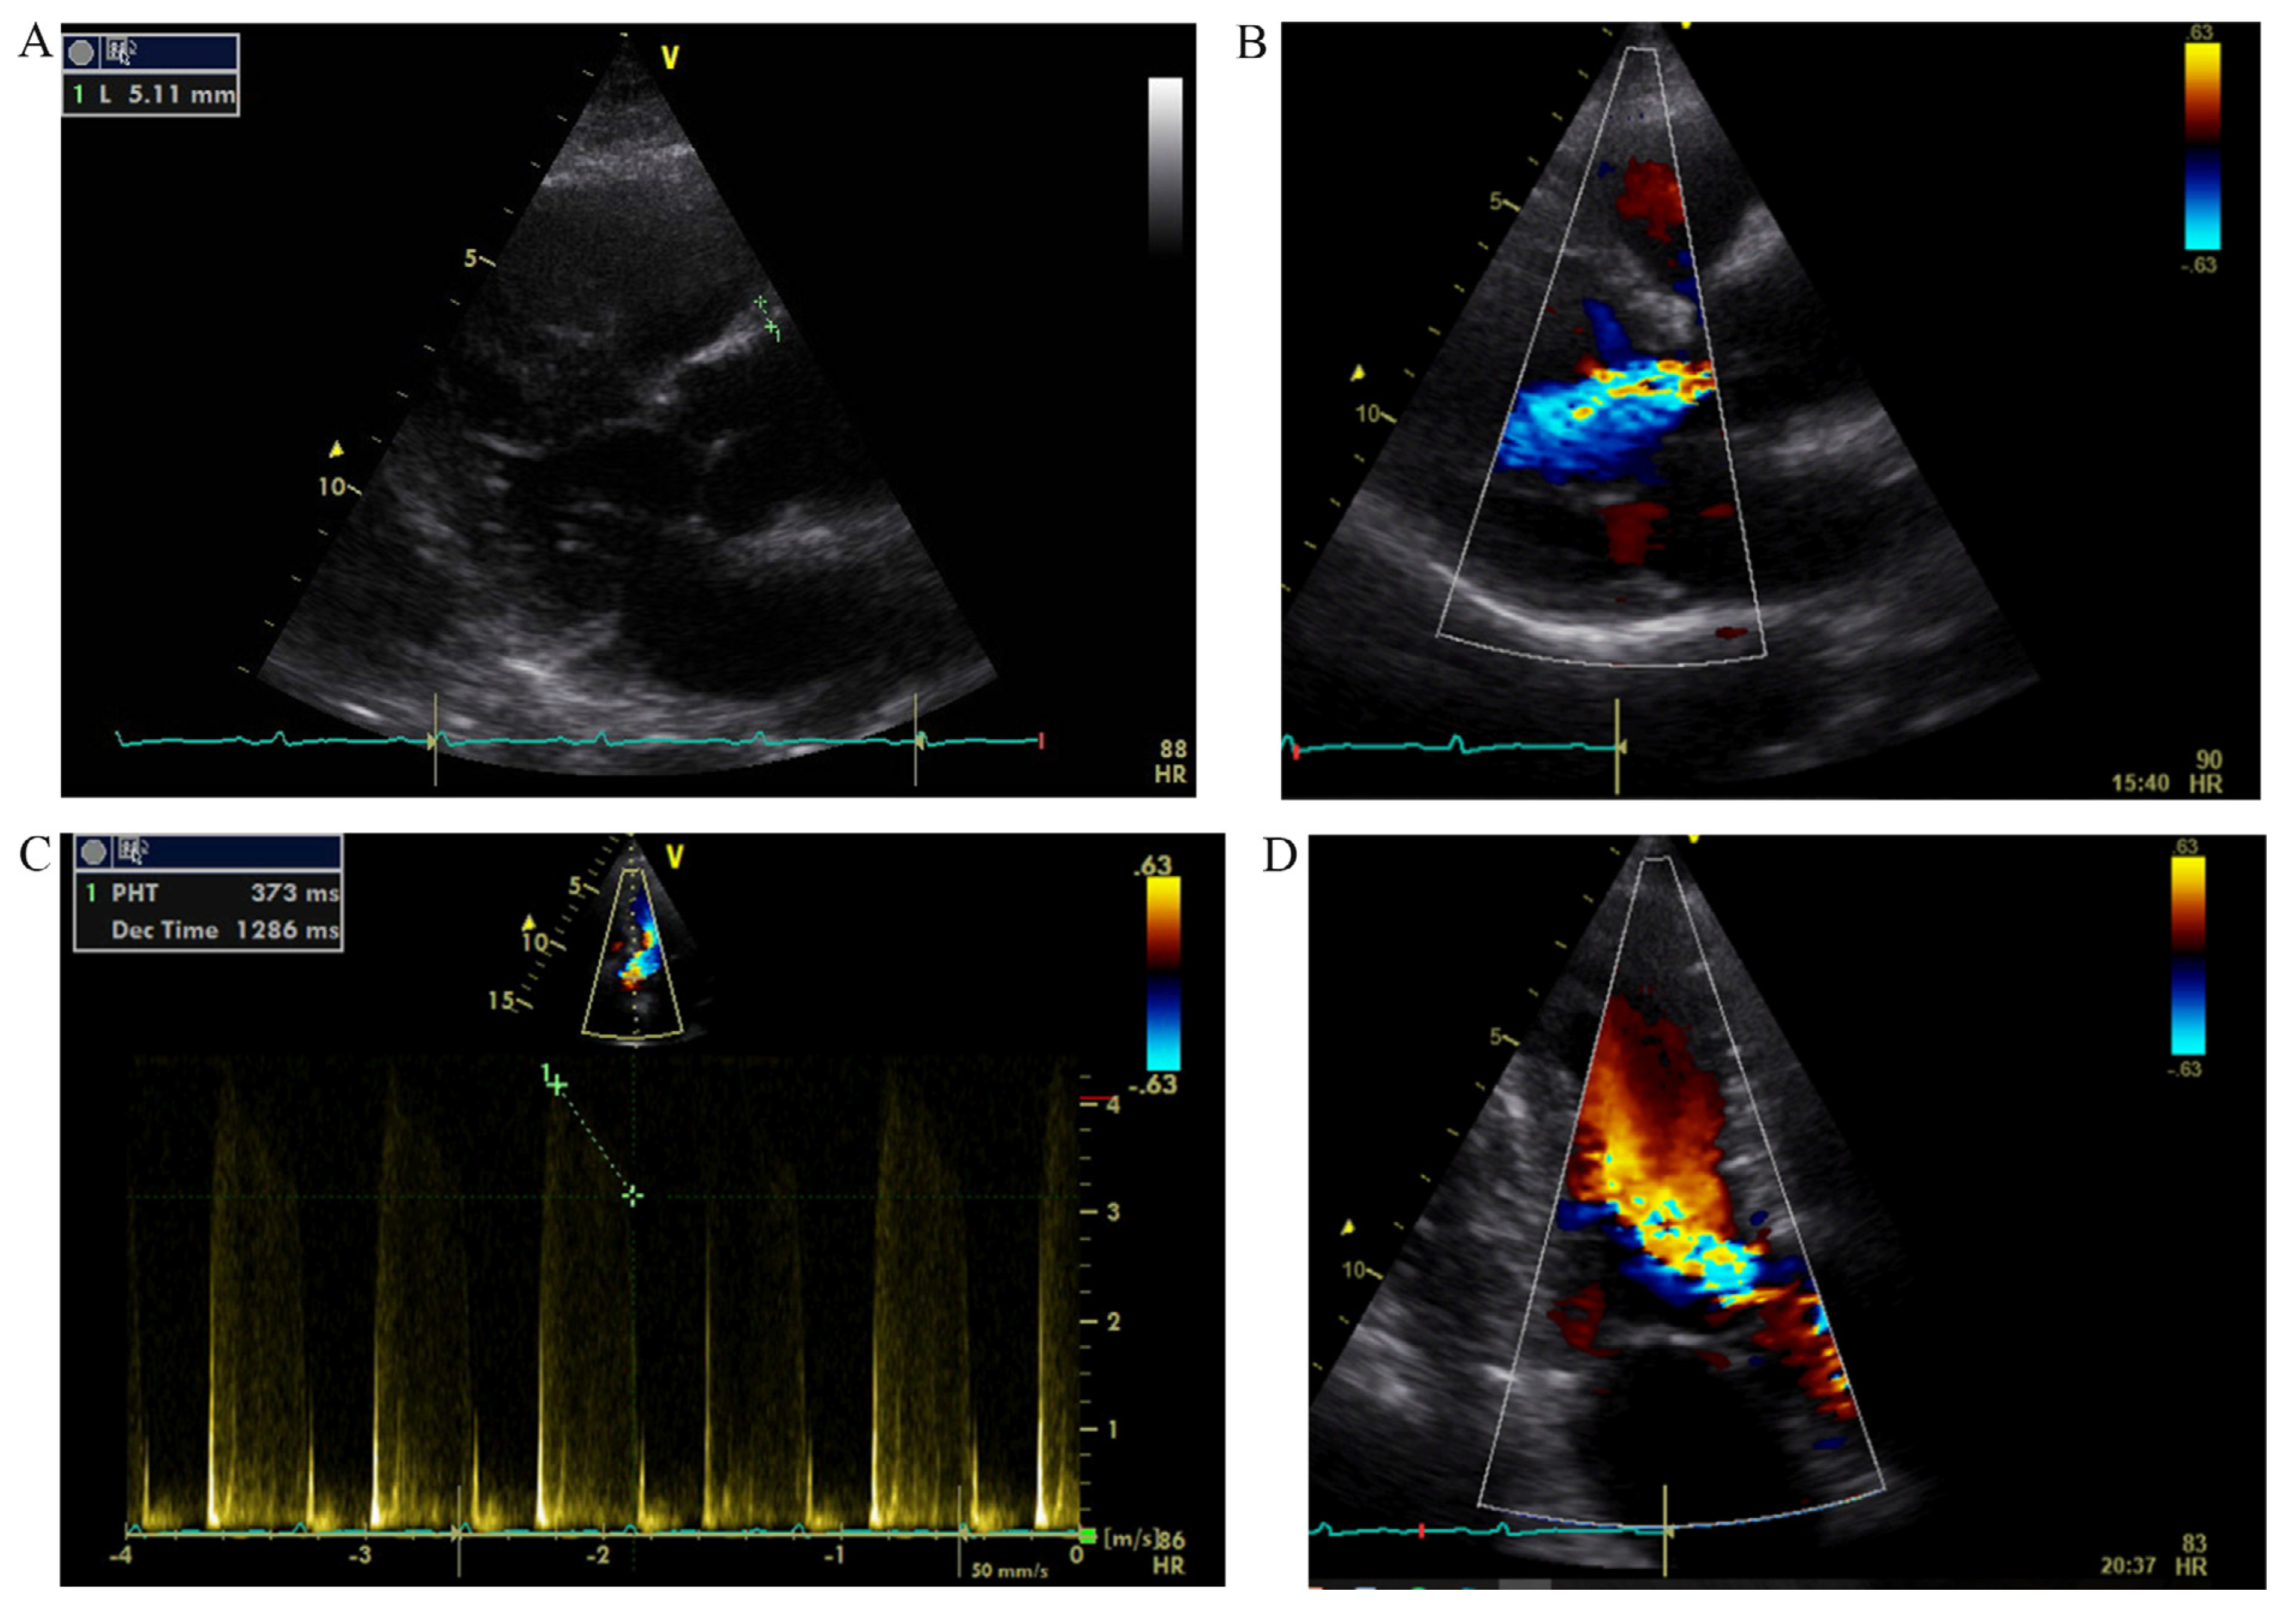

2D echocardiography revealed evidence of mildly dilatated proximal part of ascending aorta (43 mm) with a moderate regurgitation of aortic valve. The thickness of aortic walls was noted as a marker of inflammatory process. LV systolic function was normal (EF, 55%) with concentric LV remodeling (Fig. 2).

Fig. 2. - Echocardiography. A, the thickness of ascending aorta wall (5.11 mm) in a parasternal long axis view; B, aortic regurgitation (6 mm vena contracta) in a parasternal long axis view; C, the pressure half-time (PHT) – 373 ms; D, moderate aortic regurgitation in an apical 3-chamber view.